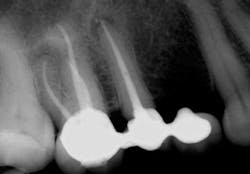

Some periapical radiolucencies (PARLs) (figure 4) may last up to five years after root canal treatment. One factor that contributes to the prolonged presence of PARLs is size of the initial lesion, such that larger lesions tend to last longer and heal at a slower rate. Location of the lesion is another factor that may contribute to this prolonged healing. Lesions in denser bone, such as the anterior mandible, tend to heal slower than lesions in less cortical bone, such as the posterior maxilla. The patient’s medical history is another factor that should be taken under consideration in such cases. Studies show that patients with diabetes, due to their lower immune system function, may require more time to heal. Some of the PAPs that tend to last can also be scar tissue in the bone.